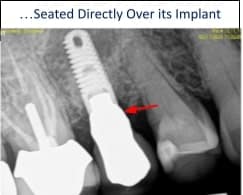

In our office, every dental implant surgery is performed using a CT scan generated surgical guide to precisely plan the future placement of the implant. With this technique, the implant is always centered inside the future overlying crown while considering any restricting bony angulations and undercuts and/or nerve and sinus locations.

The process begins with our in-house technician waxing-up an ideal crown in the space. All of these steps dramatically improve the results and safety during the procedure. Precision implant placement results in a highly aesthetic abutment and crown that mimic the replaced tooth such that you do not even know that you actually have a replacement tooth. The result: aesthetic, function, and “0” bone loss over at least a 20-year period.